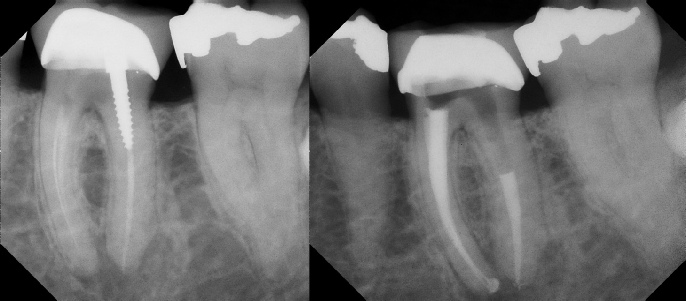

Pre-op Post-op 1 Post-op 2